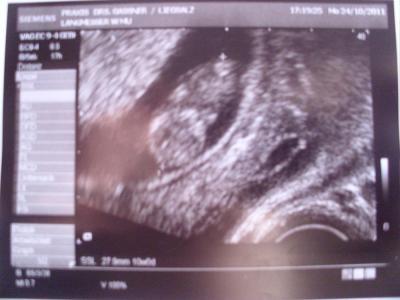

und mit dem kleinen Gumibärchen ist alles super. Länge knapp 3 cm und es hat sich schön bewegt. Arme und Beine haben wir auch schon gesehen und die Ansätze für die Fingerchen auch. Bin soooo verliebt...... . Nächster FA-Termin ist der 7.11. und dann alle 4 Wochen. ET ist der 25.5.12, aber da es eh ein Kaiserschnitt wird, so ca. 10 Tag früher. Bin soo erleichtert das alles ok ist. Anbei noch ein Bildchen, leider etwas unscharf. lg Anett

Bild zu So war ja nun gestern bei FA..................... - Forum für Mai - Mamis